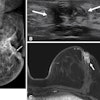

The use of preoperative breast MRI to improve surgical staging has increased, especially among women with dense breasts, extensive ductal carcinoma in situ (DCIS), and lobular histology, the team explained. But Black women are less likely to undergo this exam -- putting them at risk of additional surgery. Ginzberg's group investigated whether the use of preoperative MRI after breast cancer diagnosis varies by race and insurance type and whether undergoing the exam is associated with downstream surgical management.

The authors referred to a number of studies that have shown disparities in the use of MRI after breast cancer diagnosis, citing four that found that the likelihood of undergoing preoperative MRI before breast cancer treatment was higher for white women compared to Black women. They noted that these studies did not adjust for breast density, "a key characteristic that influences the clinical value of breast MRI and is also correlated with patient race."